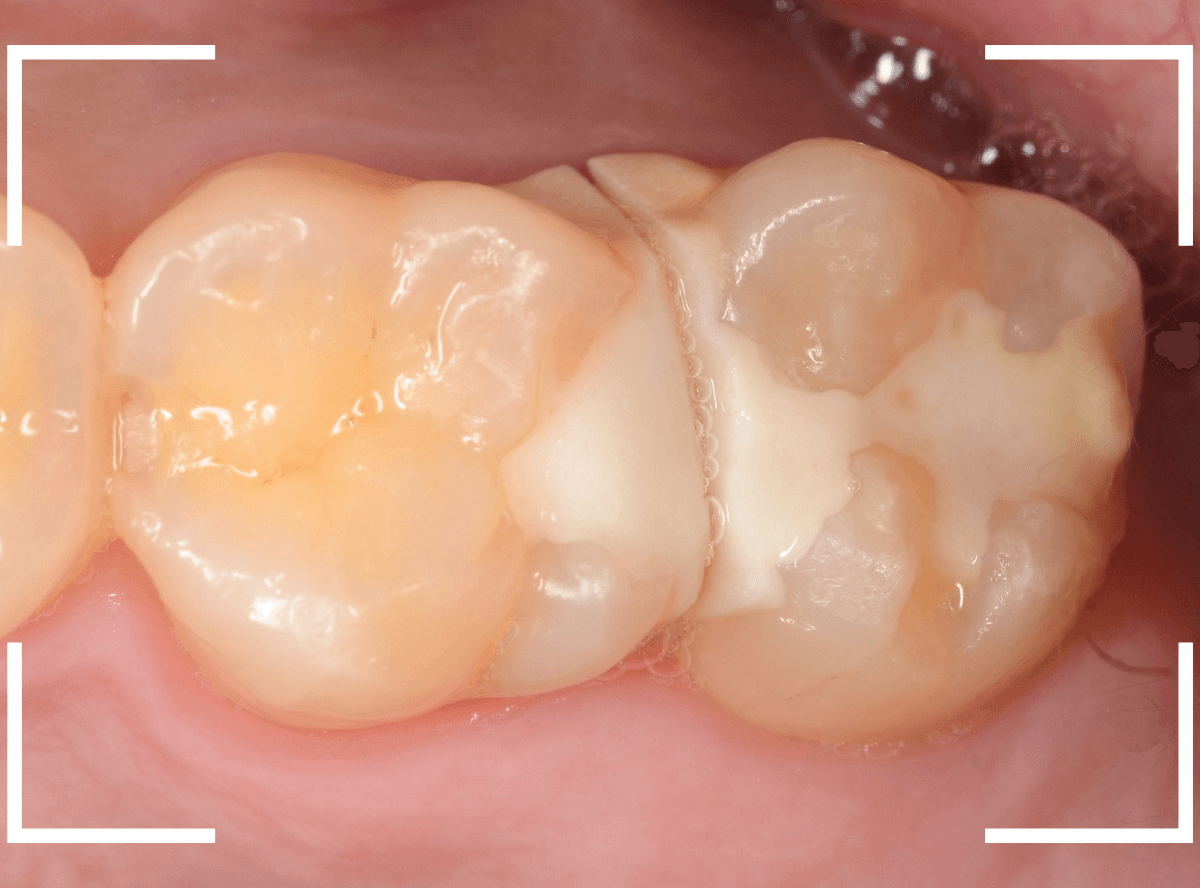

Case.29

舌のそばの虫歯とセラミック治療

下の奥歯が虫歯になった患者さんのケースです。

〇部が虫歯の部分です。

写真で見てわかるように、常に舌が歯に触っているような状況です。

このような場合、虫歯を見つけづらいですし、治療の難易度もあがります。

虫歯の治療を開始します。

隣の歯とのすき間を中心に広い虫歯になっていました。

虫歯治療後、特に症状もなく経過観察できましたので、つめものを作る治療に入ります。

セラミック治療をご希望されましたので、

小臼歯をE-MAX・インレー、

大臼歯をジルコニア・インレーで処置することになりました。